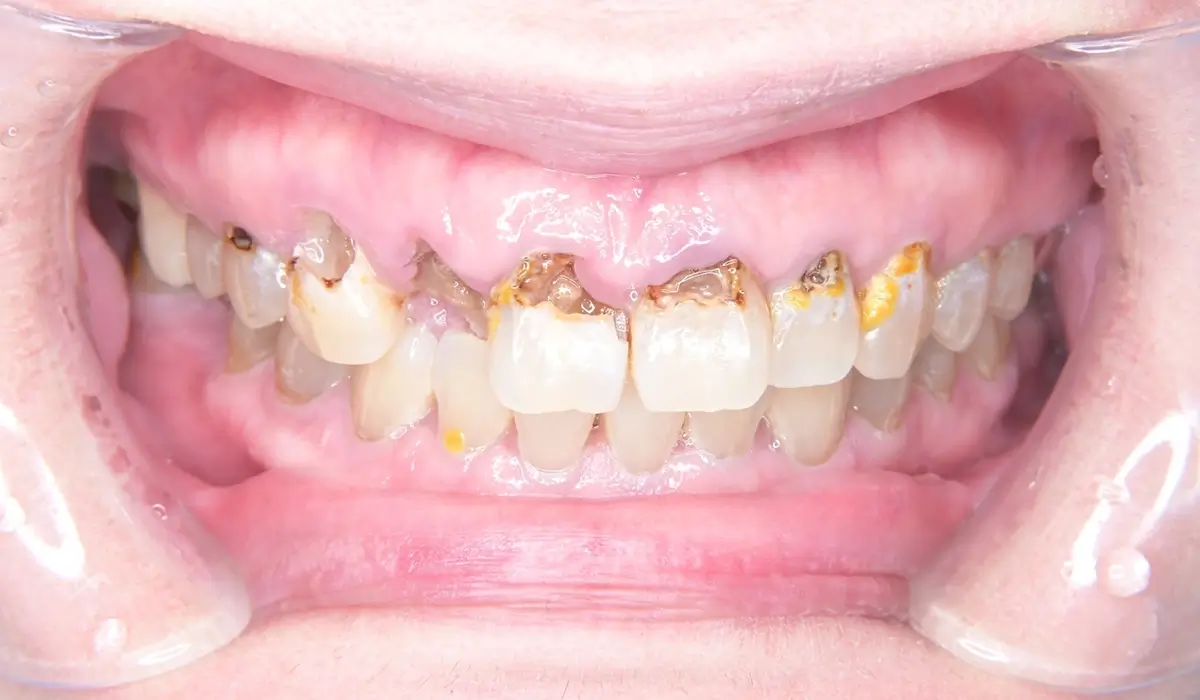

進行したカリエスと歯周病に対して全顎治療を行った症例報告です。

こちらが術前の口腔内写真になります。

問題点としては前歯部、臼歯部で進行したカリエスおよび前歯部歯肉増殖症、広範型慢性歯周炎StageⅡ GradeAが挙げられます。本症例では前歯部の審美性の回復について患者様との話し合いのうえセラミック修復による治療を選択しました。